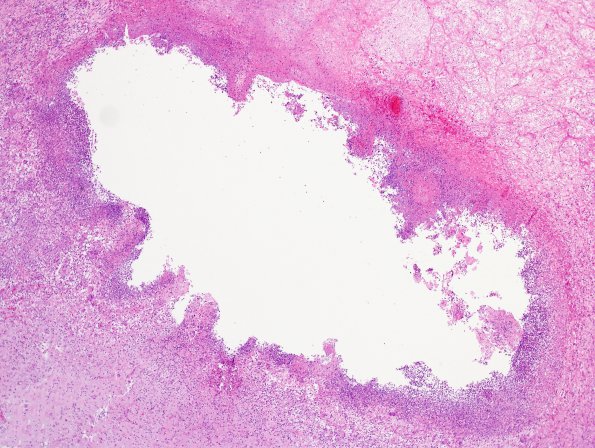

Washington University Experience | INFECTION | Fungus | Cryptococcosis | 2 Cryptococcoma | 2A2 Cryptococcoma (Case 2) H&E 4

Higher magnification of the lesion is missing much of the necrotic center and shows a complex inflammatory reaction within the wall, seen at higher magnification in the subsequent images. (H&E)